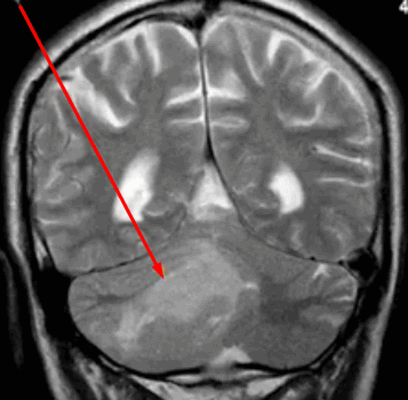

Опухоль мозжечка на МРТ (указана стрелкой)

Опухоли головного мозга долгое время диагностировали исключительно по клиническим признакам, часто слишком поздно. С появлением нейровизуализационных методов стало возможным выявление опасных патологий на ранних этапах их развития. Уже на первых стадиях формирования опухоль головного мозга на МРТ отчетливо видна, а врачи могут планировать дальнейшие действия. Ранняя диагностика увеличивает шансы на выздоровление даже при онкологических заболеваниях.

По тому, как выглядит опухоль мозга на МРТ, врачи делают предположения о ее природе. Однозначных утверждений быть не может, так как верификацию образований осуществляют с помощью гистологического анализа. Характерными признаками злокачественных опухолей головного мозга на снимках МРТ являются:

- неправильная их форма;

- нечеткие контуры новообразований;

- выраженный перифокальный отек;

- масс-эффект (смещение близлежащих структур);

- гидроцефалия;

- неоднородное накопление контраста (иногда вообще не накапливают);

- "пестрота" опухоли (кровоизлияния, некрозы и/или кисты в структуре) и др.